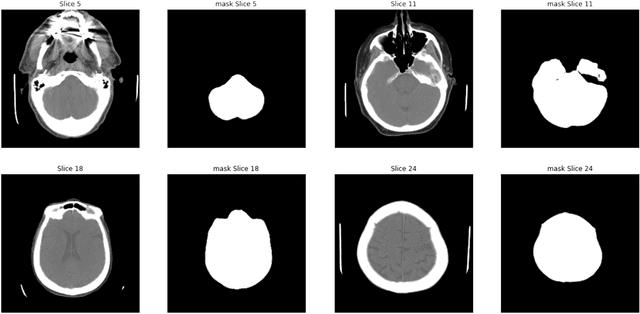

Abstract:As interest in applying machine learning techniques for medical images continues to grow at a rapid pace, models are starting to be developed and deployed for clinical applications. In the clinical AI model development lifecycle (described by Lu et al. [1]), a crucial phase for machine learning scientists and clinicians is the proper design and collection of the data cohort. The ability to recognize various forms of biases and distribution shifts in the dataset is critical at this step. While it remains difficult to account for all potential sources of bias, techniques can be developed to identify specific types of bias in order to mitigate their impact. In this work we analyze how the distribution of scanner manufacturers in a dataset can contribute to the overall bias of deep learning models. We evaluate convolutional neural networks (CNN) for both classification and segmentation tasks, specifically two state-of-the-art models: ResNet [2] for classification and U-Net [3] for segmentation. We demonstrate that CNNs can learn to distinguish the imaging scanner manufacturer and that this bias can substantially impact model performance for both classification and segmentation tasks. By creating an original synthesis dataset of brain data mimicking the presence of more or less subtle lesions we also show that this bias is related to the difficulty of the task. Recognition of such bias is critical to develop robust, generalizable models that will be crucial for clinical applications in real-world data distributions.